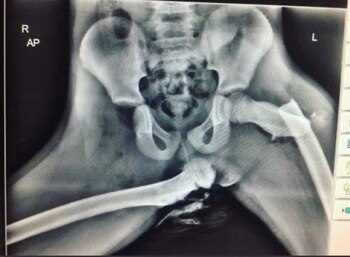

El video ilustra cómo esta postura puede ocasionar fracturas en los huesos, dislocaciones de la pelvis y daños en la columna vertebral. Además, el choque de las rodillas contra la cabeza puede generar lesiones cerebrales permanentes. Según el análisis presentado en el material, estas consecuencias no son exageraciones, sino riesgos reales que han sido documentados por estudios y organismos especializados en seguridad vial.